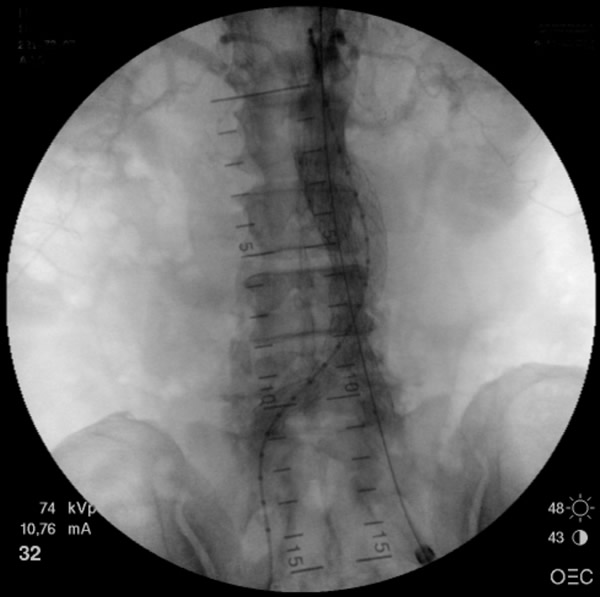

- The main trunk is flushed with heparinized solution, advanced into the proximal neck, positioned just inferior to the lowest renal artery, and oriented so that the contralateral limb gate can be easily accessed. The orientation of the contralateral gate is performed using the manufacturer’s radiopaque markers at the crown of the trunk and/or the stent graft bifurcation under fluoroscopic guidance. A repeat angiogram is commonly performed to reconfirm the positioning of the device within the aorta. Subsequently, the main trunk is deployed (Figures 2, 3), opening the contralateral limb gate.